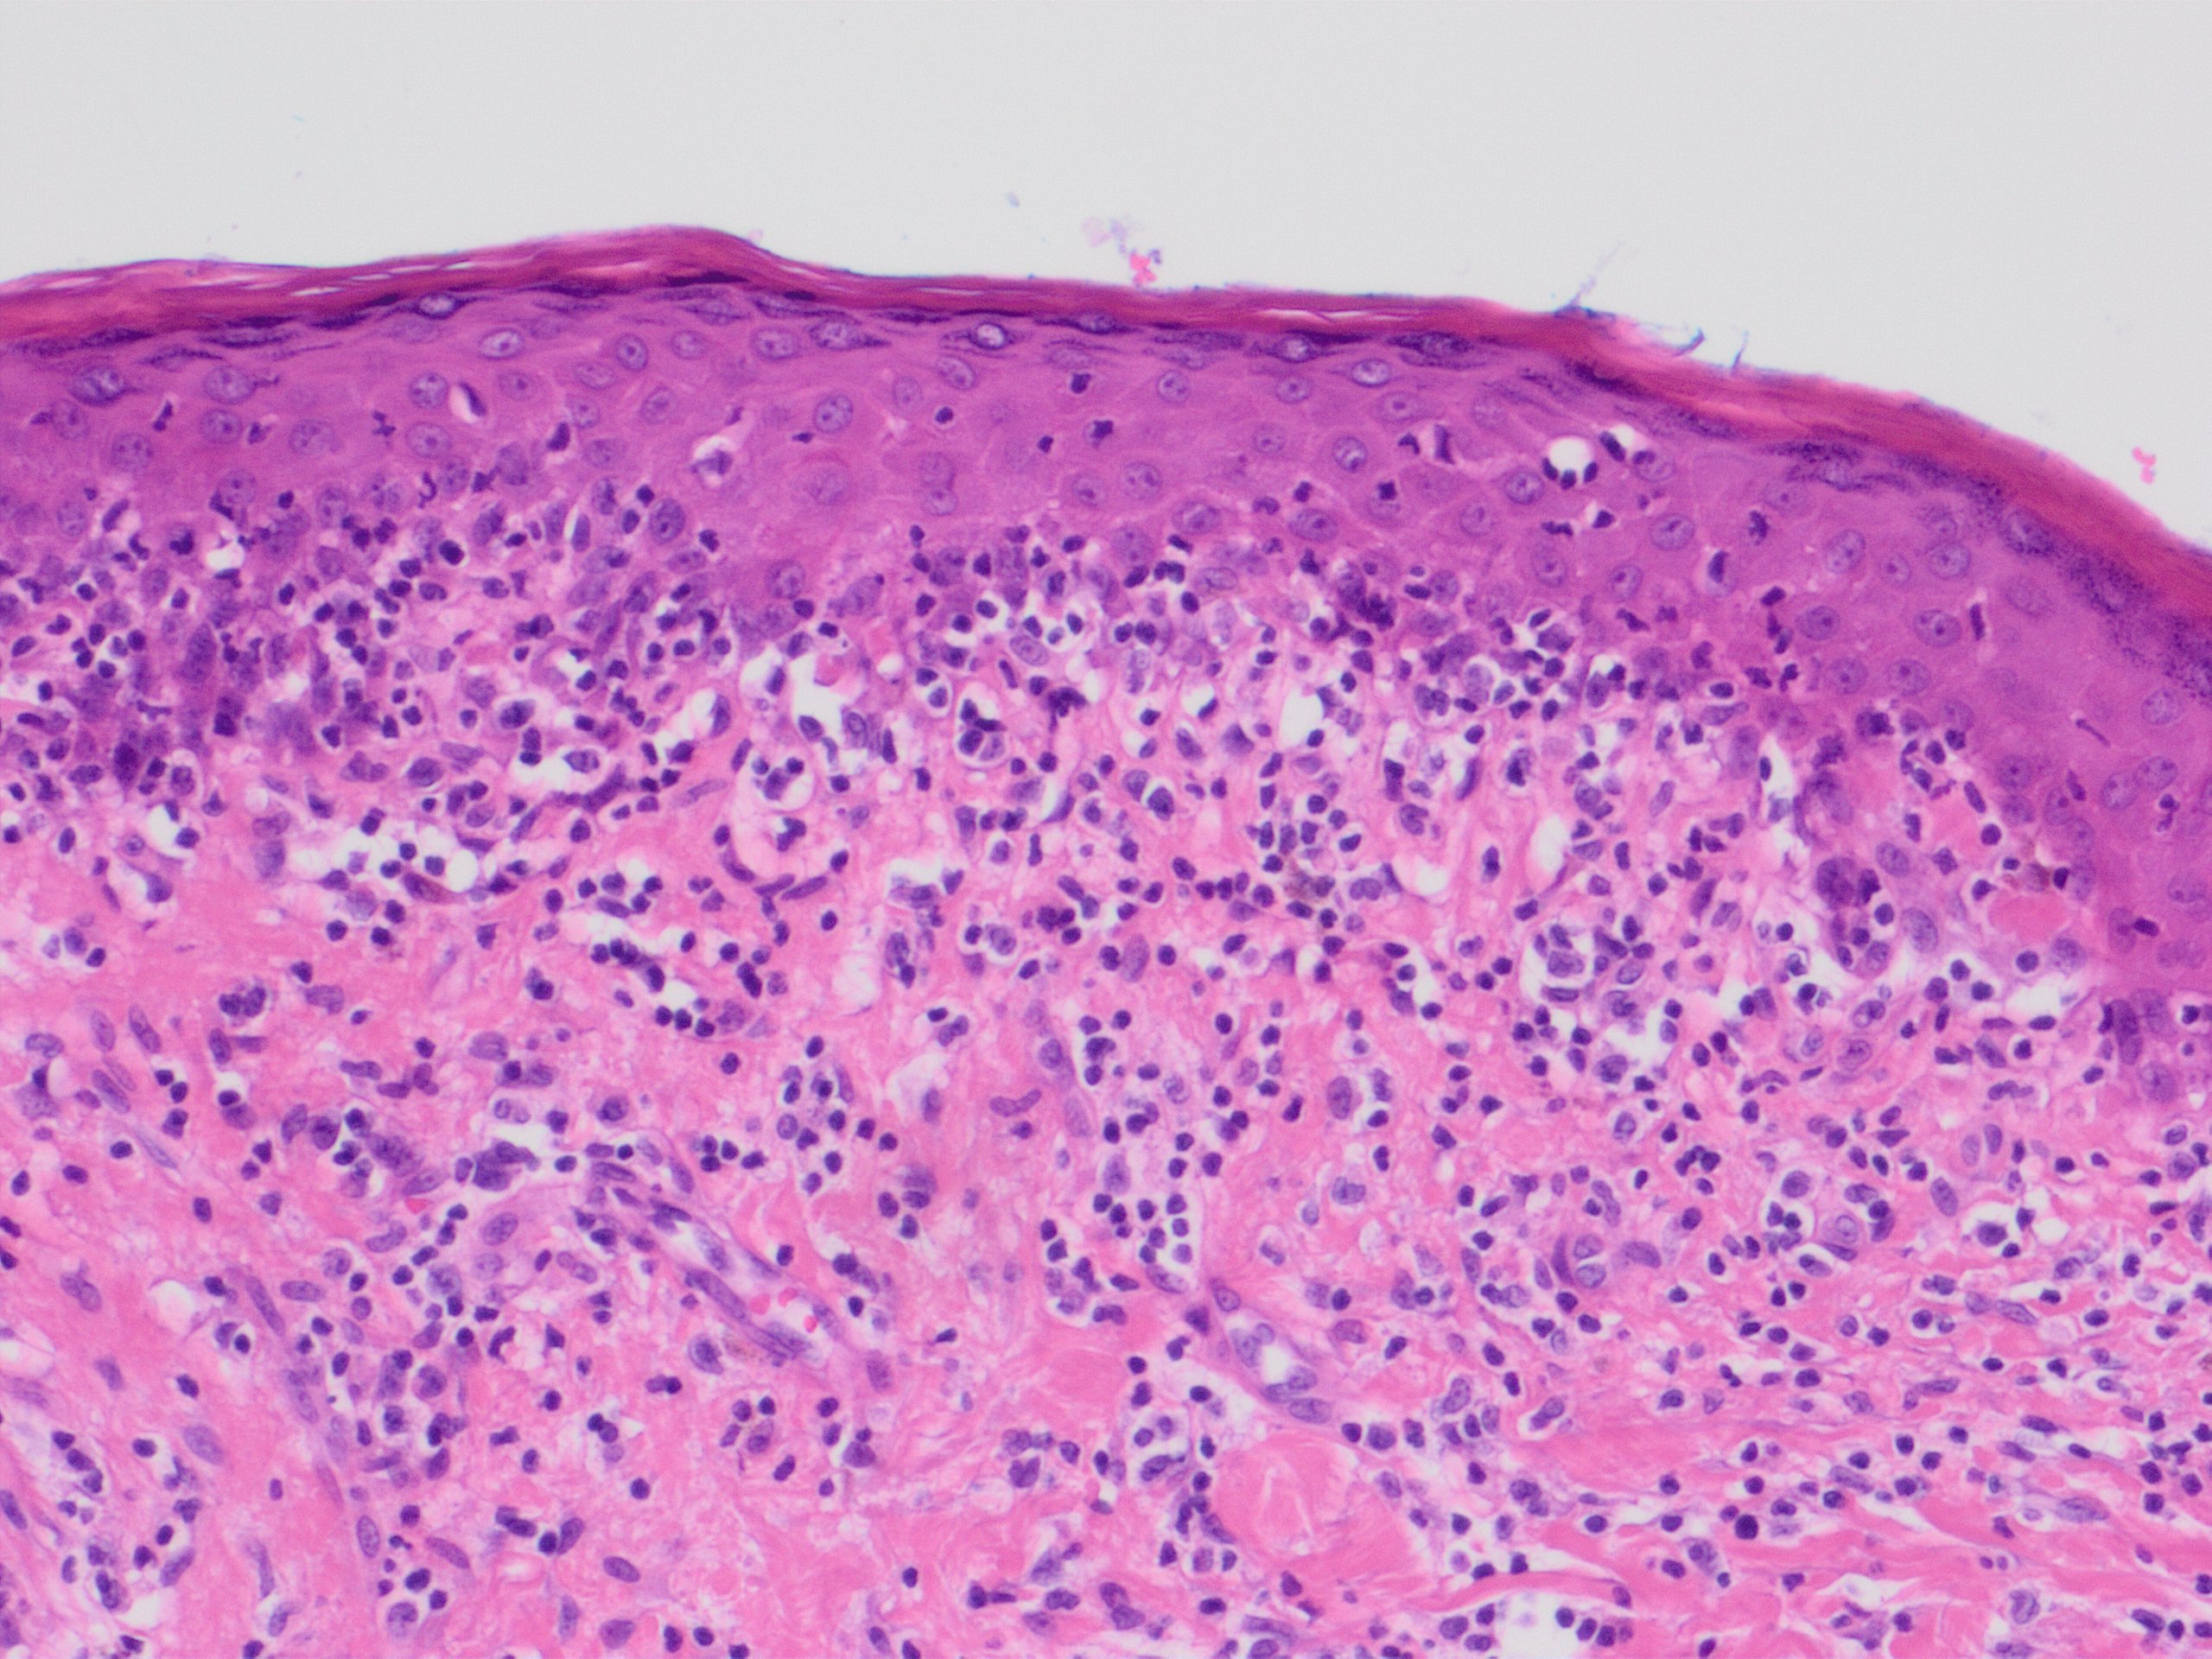

18- Case ( presented by Nastassia Nardini)